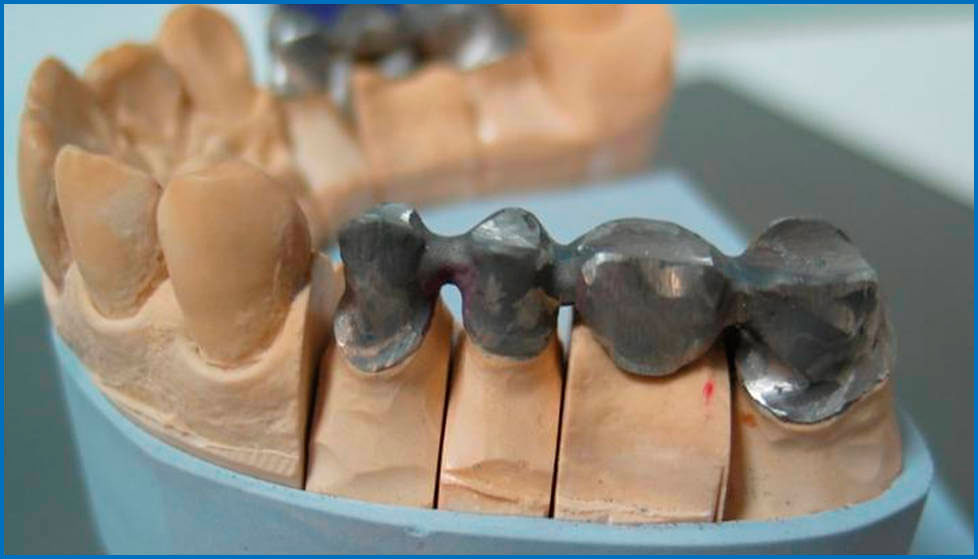

Стоматология: коронки и мостовидные протезы